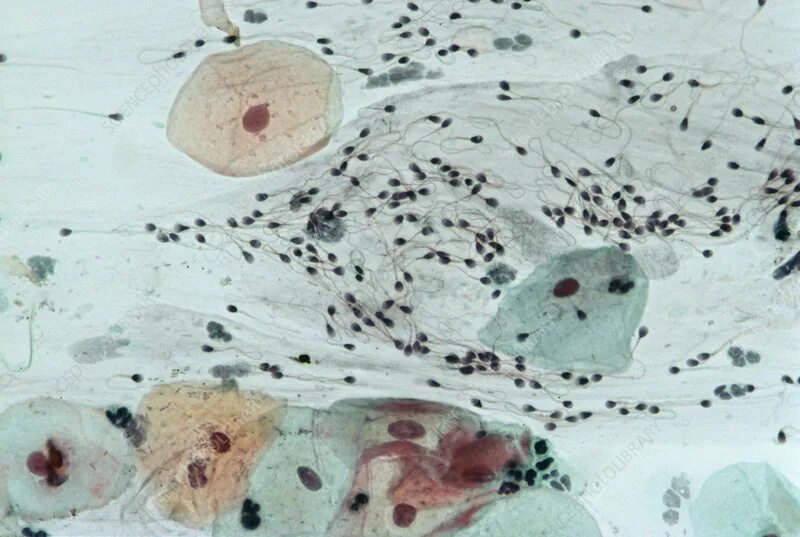

Эндоцервикс клетки метаплазированного эпителия